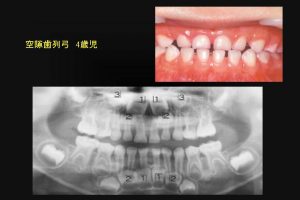

ところで切端咬合の乳歯前歯には空隙がある小児が多い。

4歳児の乳歯空隙歯列弓のパノラマレントゲン撮影を行うと、下顎の永久4前歯は顎骨内で並列になっており、

永久歯はきれいな歯列になることは容易に想像できる。(図5)

図5

図5:乳歯の切端咬合は、空隙歯列弓が多い。